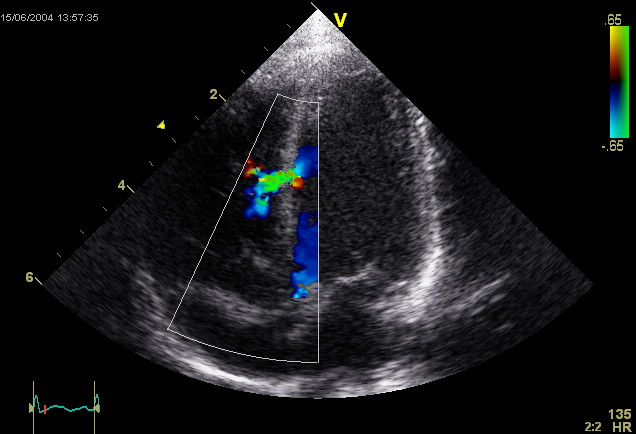

ECOCARDIOGRAFIA PEDIATRICA

Estudio del corazón y de la circulación, desde el período de recién nacido hasta la adolescencia.